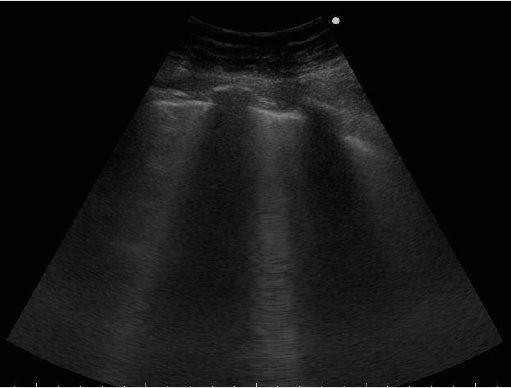

Finally we report the LU performed immediately before the discharge (Figures 5 & 6), showing more ventilated areas characterized by the presence of A lines and the reduction of B lines, that according to the literature, is an ultrasound finding of GGO improvement [11-12].